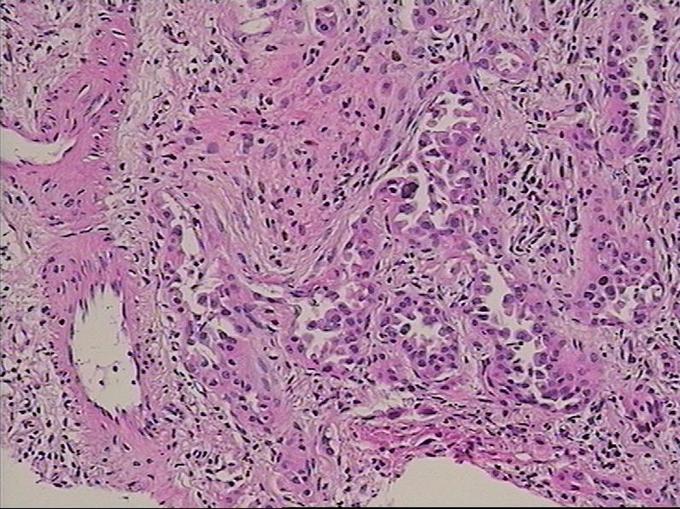

诊断为右肺上叶前段,下叶背段高分化腺癌,T4N0M0(IIIA)期 行胸腔镜手术楔形切除术,术后测EGFR阳性,给予分子靶向药物埃克替尼治疗

患者无任何症状,体检发现肺部小结节影,观察2月,未见缩小,似有轻度增大,入院后经CT引导下肺穿刺活检提示高分化腺癌,行手术治疗。 周围型肺癌早期影像学表现为孤立的肺内结节或肿块,通常有分叶征,毛刺征,空泡征,支气管充气征,坏死液化或空洞形成。此患者仅表现为淡薄的渗出影,小结节影,观察2月没有变化后,经穿刺证实肺癌,因此对肺部小结节影,斑片影,不吸收,无钙化的要特别注意肿瘤可能。